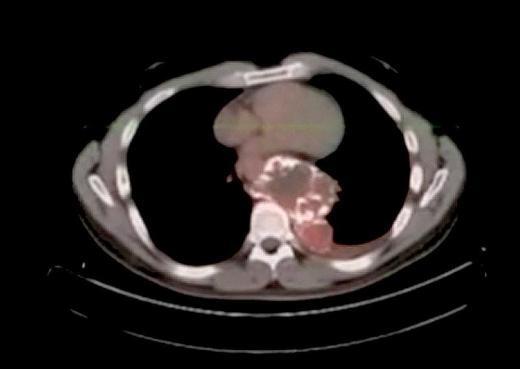

8. Bu CAT scan görüntüsü ise Brezilya'nın Sao Paulo kentindeki Congonhas Havalimanı'nda yakalanan İrlandalı bir erkeğe ait. Karın bölgesinden alınan bu görüntülerde kapsüllere doldurulmuş 830 gram kokain bulunuyor.

Bu CAT scan görüntüsü ise Brezilya'nın Sao Paulo kentindeki Congonhas Havalimanı'nda yakalanan İrlandalı bir erkeğe ait. Karın bölgesinden alınan bu görüntülerde kapsüllere doldurulmuş 830 gram kokain bulunuyor.